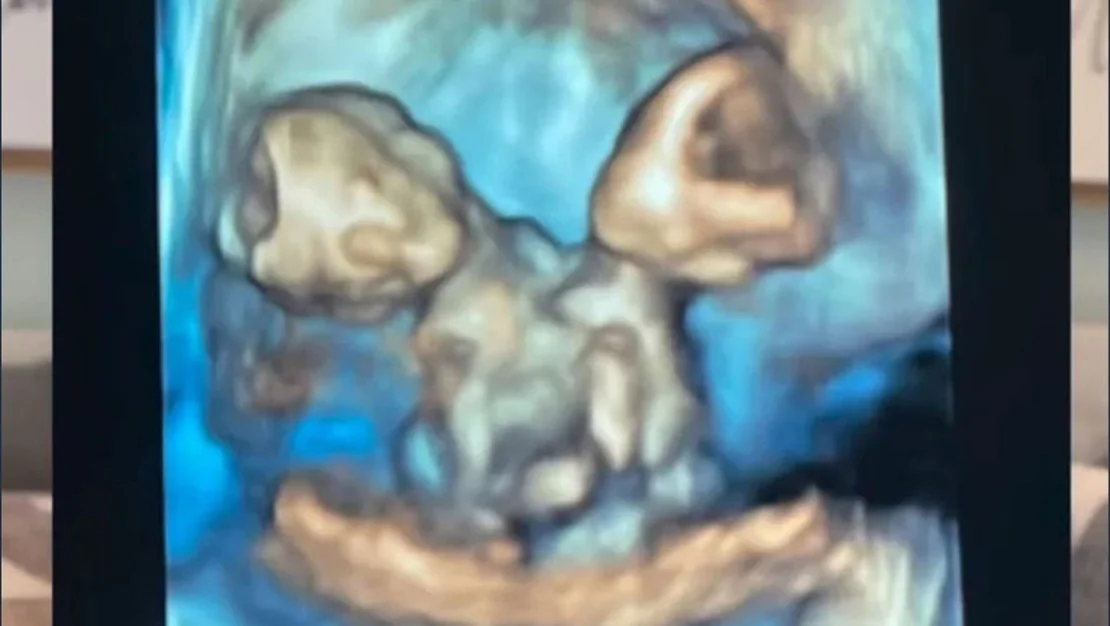

ABD’nin Michigan eyaletinde yaşayan Nicole ve Austin LeBlanc çifti, ilk bebeklerini beklerken büyük bir mutluluk hissediyor. Ancak bu mutluluk, gebeliğin yedinci haftasında yapılan kontroller sırasında bazı sıkıntılarla karşılaştı. Yapılan ultrason muayenesinde sadece bir kalp atışı duyulmasına rağmen ikiz gebelik şüphesi belirdi. Kısa süre sonra, Nicole’un şiddetli karın ağrısıyla hastaneye kaldırılmasıyla olayın gerçek yüzü ortaya çıktı. Anne adayı, tek kalp, karaciğer, bağırsak, diyafram ve göbek kordonunu paylaşan ikiz kız bebeklere hamile olduğunu öğrendi.

Nicole, 32. haftada sezaryenle ikizlerini dünyaya getirdi. Bebeklere Maria Therese ve Rachel Clare isimleri verildi. Doğum sırasında Maria yüksek sesle ağlarken, Rachel uyuyordu. Nicole, “Yüzlerini görmek ve paylaştıkları bedene şahit olmak inanılmazdı” diyerek o anları gözyaşları içinde hatırladı. Ancak, bebekler doğumdan kısa bir süre sonra, anne ve babalarının kollarında hayata gözlerini yumdu…